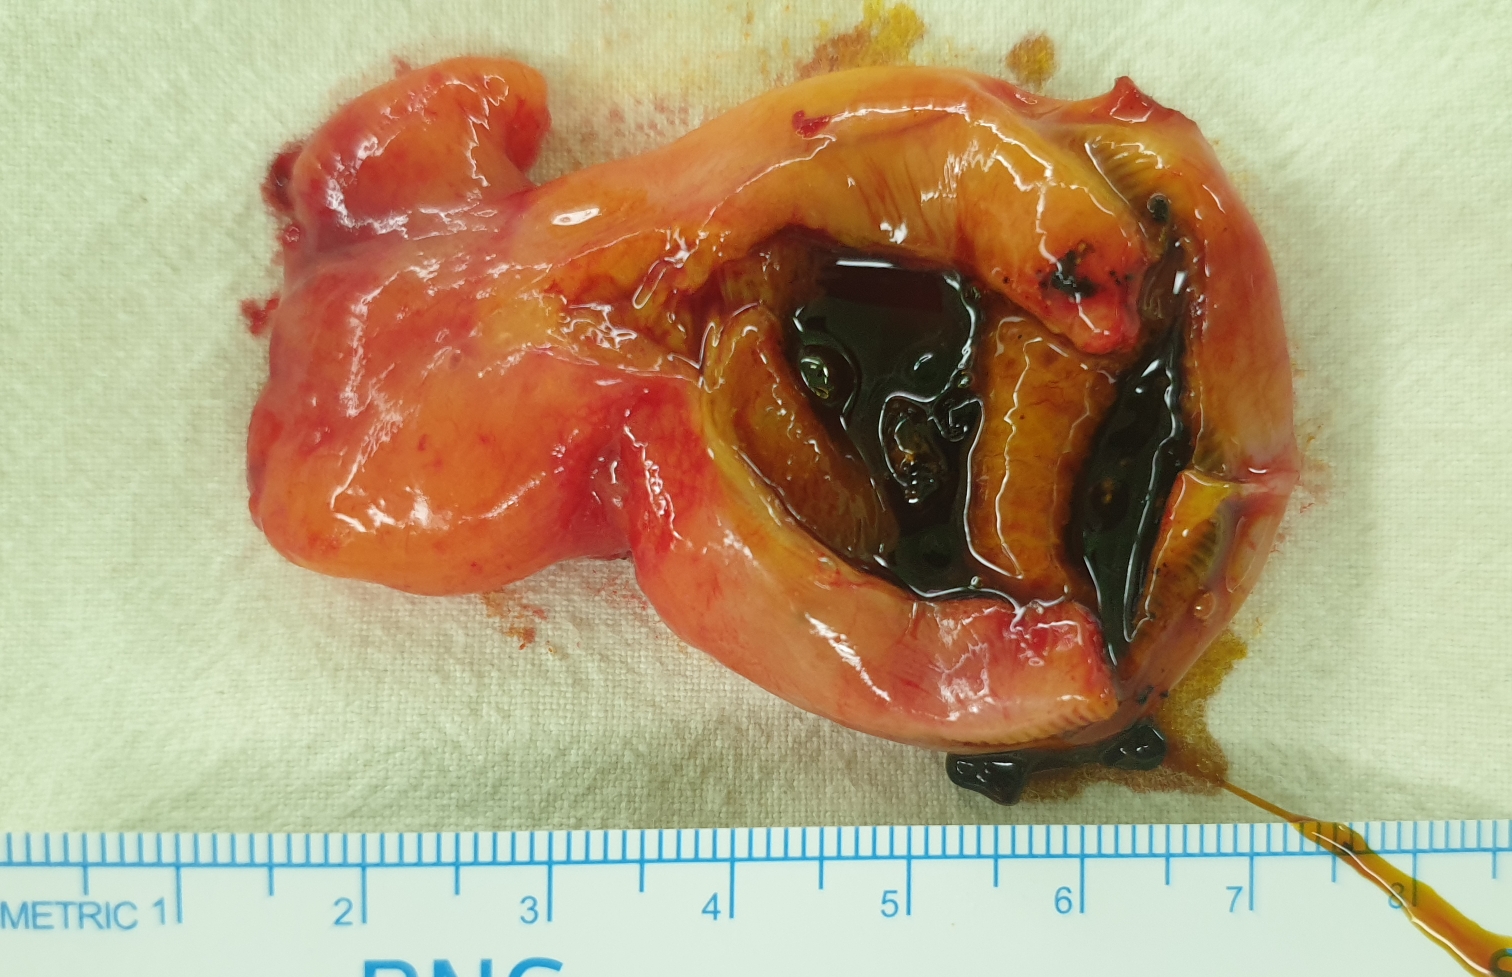

복강경 담낭절제술을 시행했습니다.

수술은 잘 끝났고 20분 걸렸습니다.